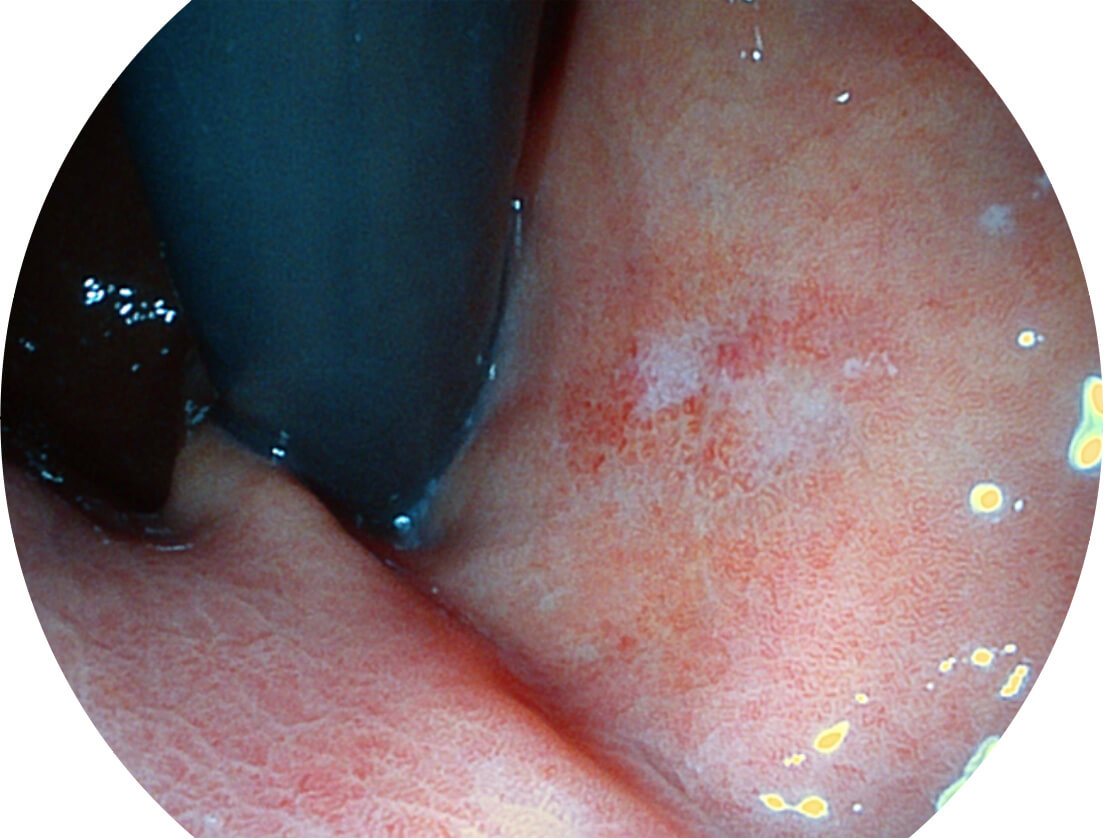

Versatile Intelligent Staining Technology, VIST

强调浅层黏膜结构的同时,保证照明亮度和提升浅层微血管与中层血管颜色对比度,病变边界更清晰。

白光图像

VIST图像